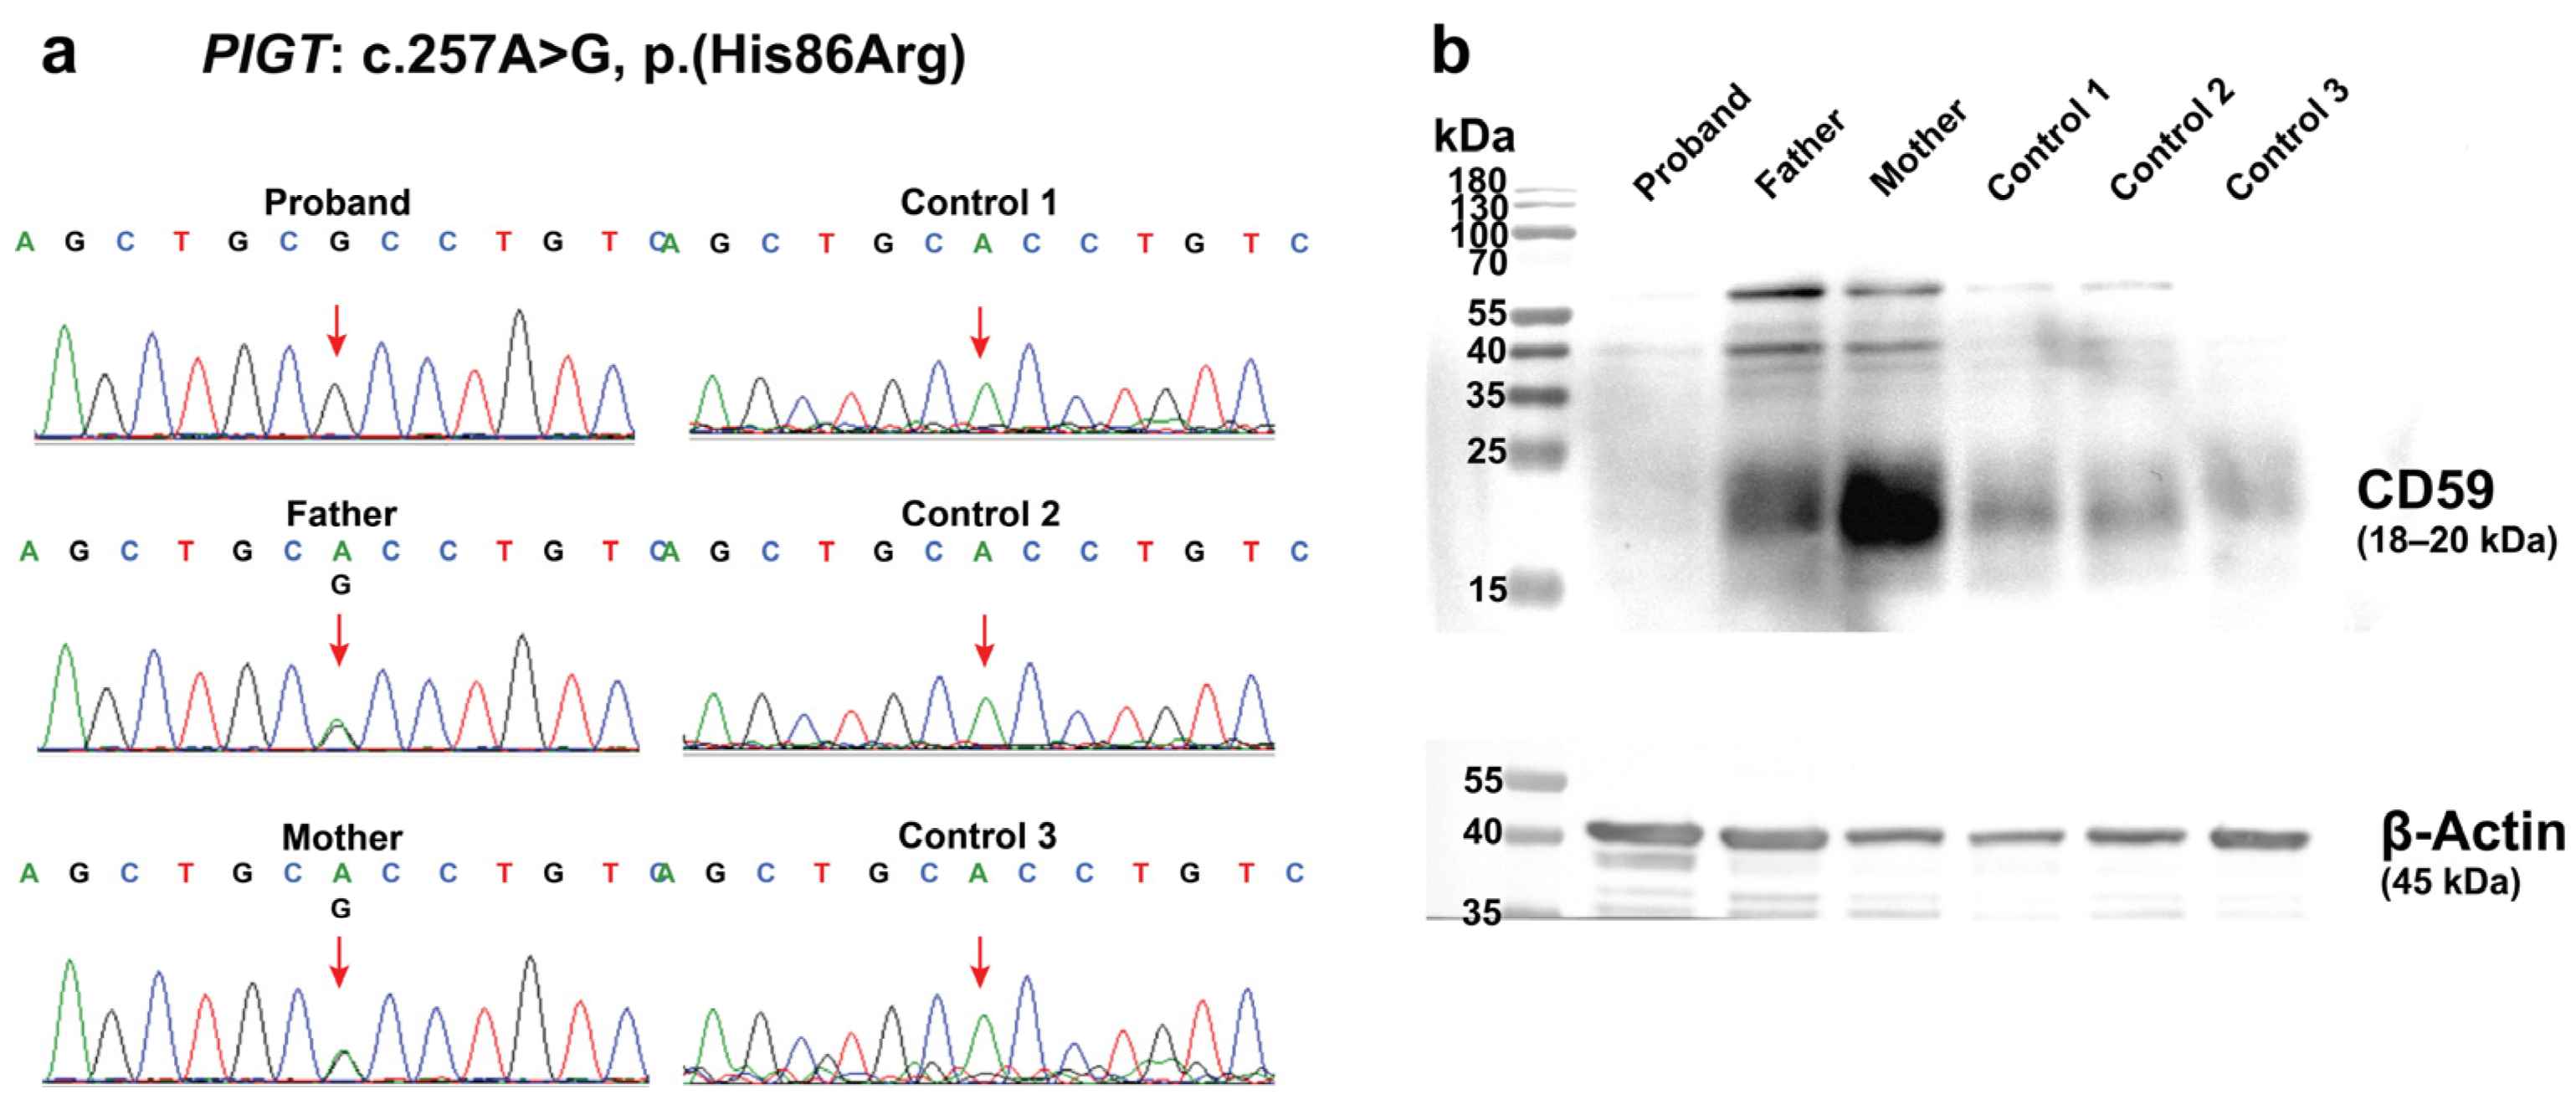

2.2. Germline Mutation Analysis

2.3. Effects of the c.257A>G on PIGT Function Demonstrated by GPI-AP Expression Analysis